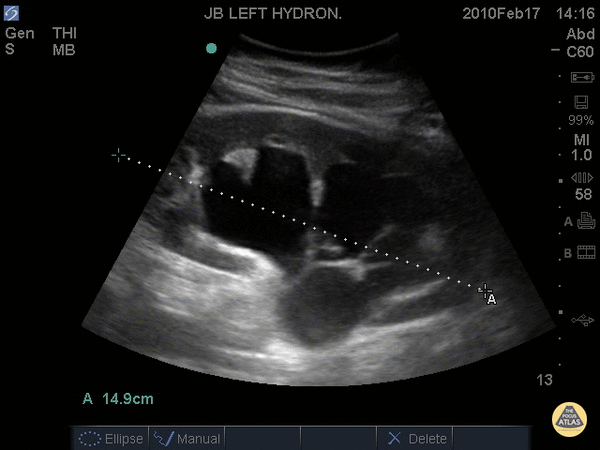

Hydronéphrose modérée

-

Bassinet et calices clairement dilatés

Aspect central très anéchogène

Parenchyme encore présent

![]()

Hydronéphrose modérée. © POCUS Atlas